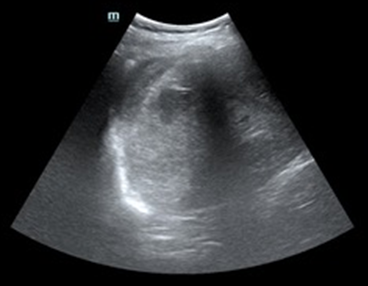

Tras varias horas en observación el paciente comienza con tendencia a la hipotensión. Permanece en observación y monitorización persistiendo hipotensión arterial con buena ventilación bilateral en la auscultación pulmonar. En la exploración abdominal presenta dolor y defensa a la palpación profunda en hipocondrio izquierdo. Se realiza Ecografía clínica a pie de cama del paciente descartando hemoneumotótax y derrame pericárdico; al explorar el abdomen se objetiva líquido libre en espacio de Morrison y eje espleno renal, con imagen compatible con rotura del parénquima esplénico. Gasométricamente se objetiva anemización con caída de cifras de Hb de 15,7 g/dl en análisis inicial a 13,8 g/dl. Se solicitan pruebas cruzadas, se reservan hemoderivados y se contacta con cirugía para traslado del paciente a quirófano.